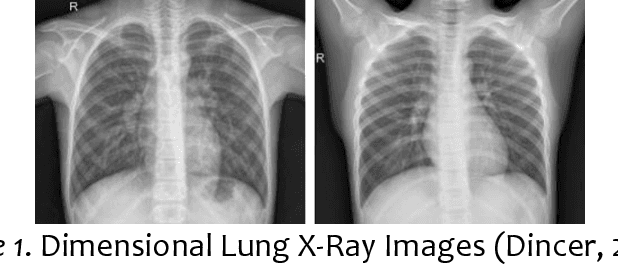

Abstract:This study focuses on the application of a specific subfield of artificial intelligence referred to as computer vision in the analysis of 2-dimensional lung x-ray images for the assisted medical diagnosis of ordinary pneumonia. A convolutional neural network algorithm was implemented in a Python-coded, Flask-based web application that can analyze x-ray images for the detection of ordinary pneumonia. Since convolutional neural network algorithms rely on machine learning for the identification and detection of patterns, a technique referred to as transfer learning was implemented to train the neural network in the identification and detection of patterns within the dataset. Open-source lung x-ray images were used as training data to create a knowledge base that served as the core element of the web application and the experimental design employed a 5-Trial Confirmatory Test for the validation of the web application. The results of the 5-Trial Confirmatory Test show the calculation of Diagnostic Precision Percentage per Trial, General Diagnostic Precision Percentage, and General Diagnostic Error Percentage while the Confusion Matrix further shows the relationship between the label and the corresponding diagnosis result of the web application on each test images. The developed web application can be used by medical practitioners in A.I.-assisted diagnosis of ordinary pneumonia, and by researchers in the fields of computer science and bioinformatics.